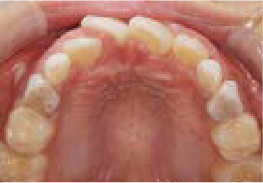

これから生えてくる永久歯のスペースがなく、歯が並ぶ余地がほとんどありませんでした。

さらに、上からあごの骨を見たところ、中央がくびれた“ひょうたん型”に変形しており、あごの成長にも偏りが見られました。

診断の結果、前歯の中心も少し左にずれており、特に犬歯が生えるスペースが足りない状態でした。

飲み込むときに下くちびるに力が入り、顔の左側にゆがみが出ている様子も確認できました。

治療を終えて

犬歯が歯ぐきの中に埋まっていたため、透明のマウスピース型装置で生えるスペースを作り正しい位置に導きました。もちろん抜歯せずに歯並びを整えることができました。お口の中がとても小さく、型どりの際にオエッとなる反応が強く、当時は装置を作るのが大変でした。しかし現在では3Dスキャナーと3Dプリンターを活用しスムーズに治療できます。

主訴・治療内容 「あごが小さいから、歯がきれいに並ばない」と他院で言われ永久歯を抜く矯正をすすめられていました。

本当に非抜歯で治療できるのか心配されていましたが、治療方法を丁寧にご説明し、お任せいただきました。

治療期間 5年

費用 550,000円(税込)